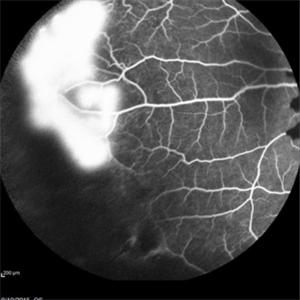

Angiography showed normal vessels posteriorly but severe capillary drop out throughout the periphery OU with scattered severe neovascularization at the edge of the capillary drop out peripherally.

Sickle Cell Retinopathy Sickle Cell RetinopathySep 13 2015 by Thomas A. Ciulla, MD, MBA, FASRS Angiography showed normal vessels posteriorly but severe capillary drop out throughout the periphery OU with scattered severe neovascularization at the edge of the capillary drop out peripherally. Note the preretinal and vitreous hemorrhage obscuring the view of the retinal vasculature. Photographer: Thomas Steele Condition/keywords: peripheral retinal neovascularization, sea fan, sickle cell retinopathy